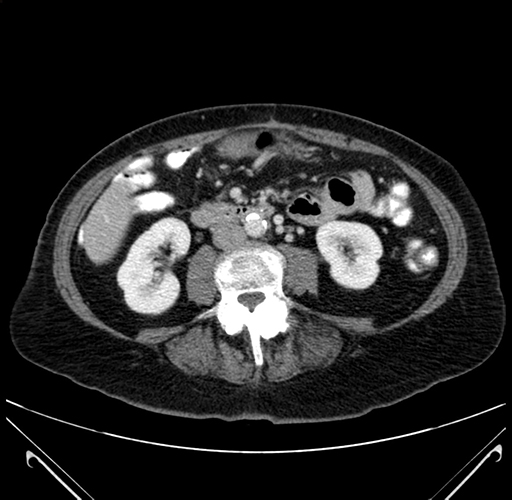

Pre-Chemo: Coronal Venous

Coronal Venous